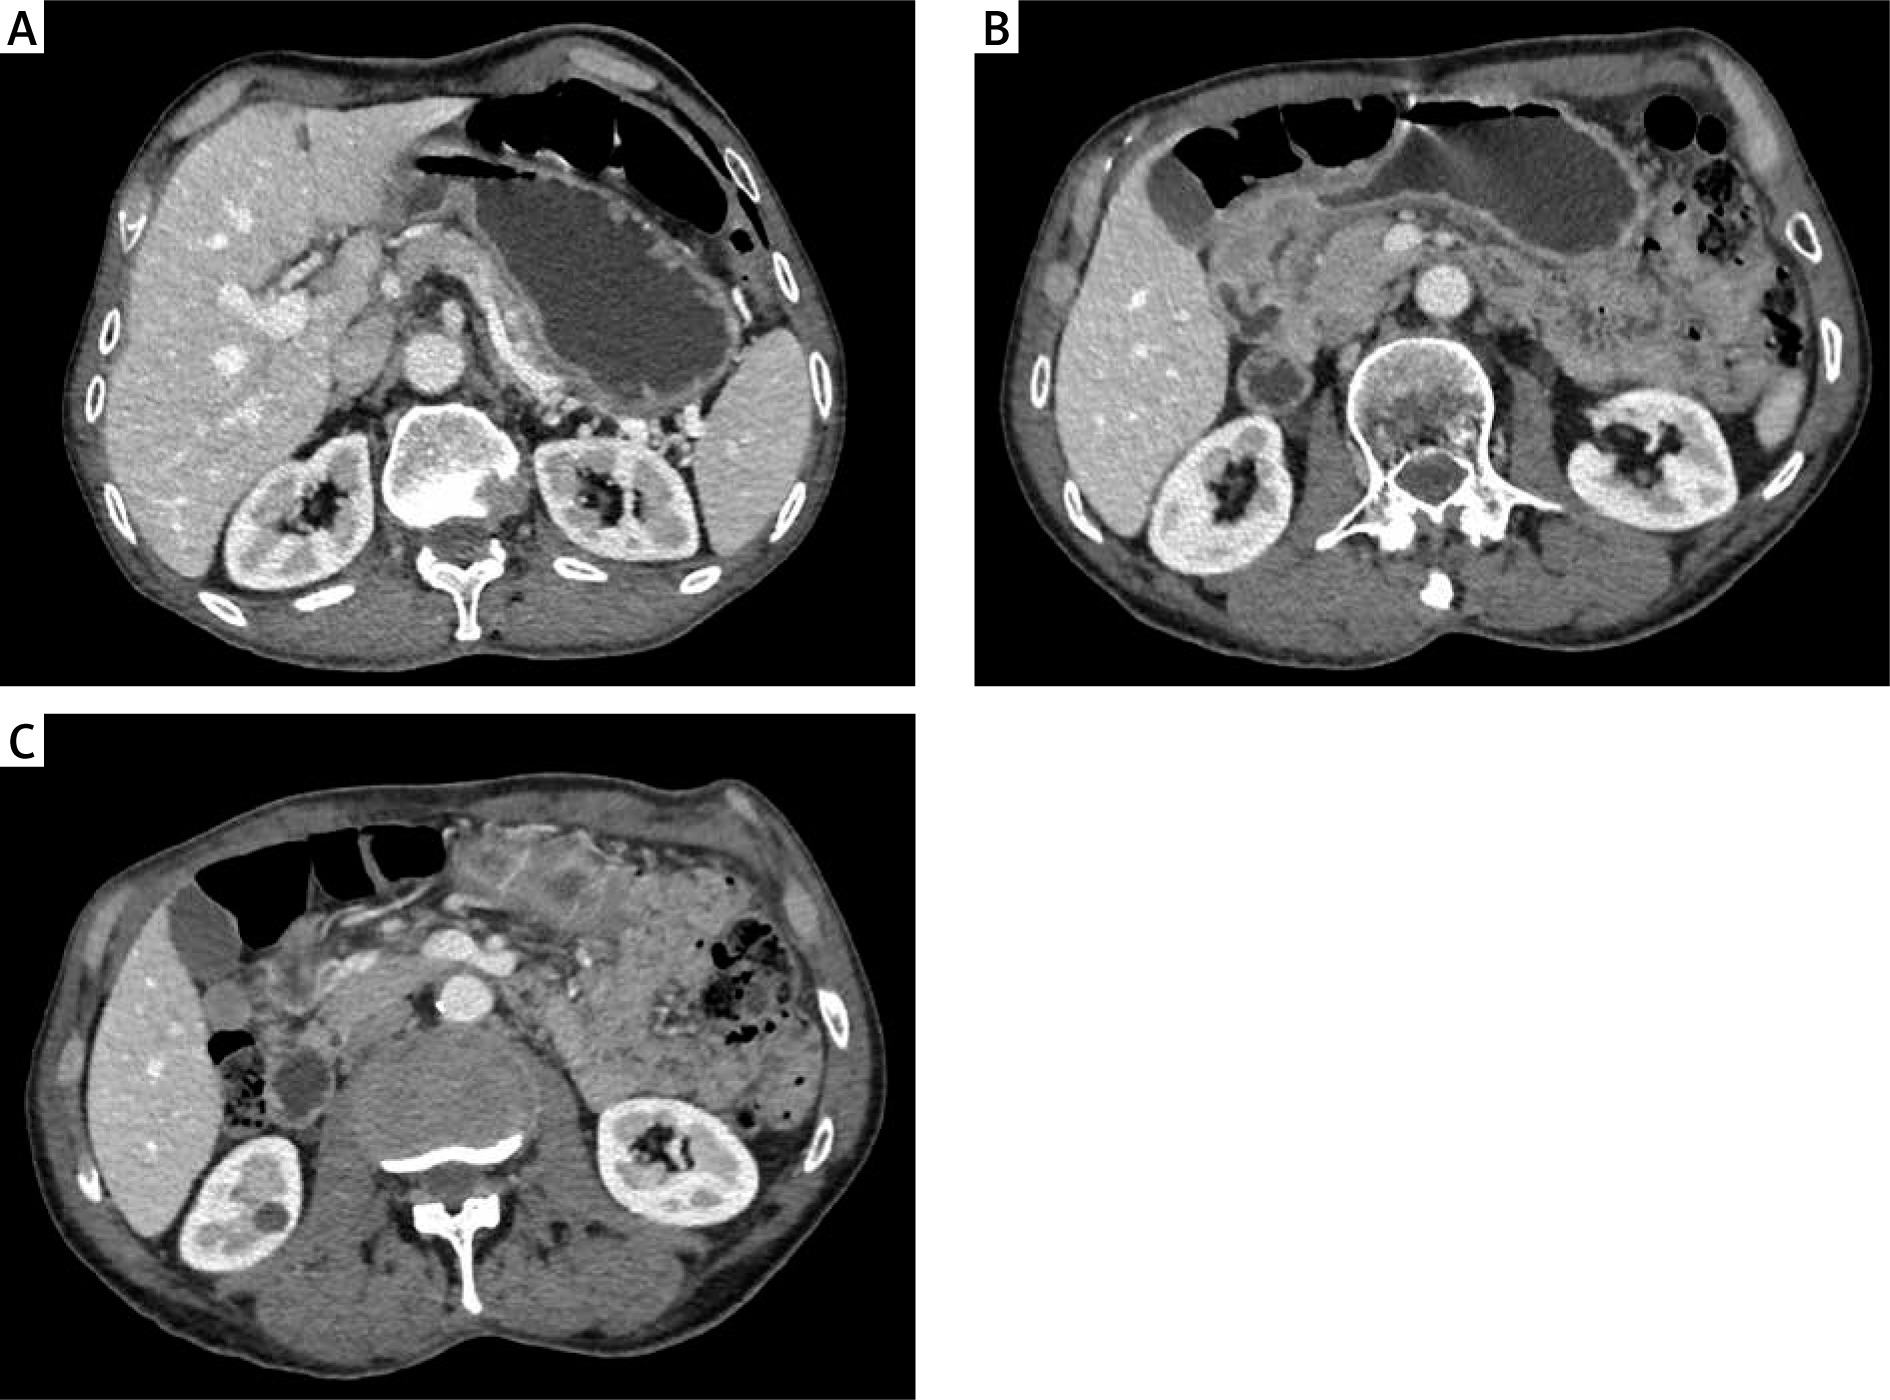

In the laboratory evaluation, haemoglobin was 12 g/dl, platelet count 272,000/ml, albumin 3.4 g/dl, total protein 6.2 g/dl, and tumour markers were normal. Upper gastrointestinal endoscopy revealed a stomach filled with solid food debris and a mass protruding from the antropyloric region of the stomach, which did not allow the passage of the scope (Figure 1). Endoscopic biopsy report of the mass showed high-grade dysplasia. Contrast-enhanced thorax, abdomen, and pelvis computer tomography showed clinical T3N+M0 gastric cancer (Figures 2 A–C). The patient was optimized for surgery and later underwent laparoscopic distal gastrectomy with D2 dissection and gastrojejunostomy with Roux-en-Y reconstruction. Intraoperatively, there were no adhesions, ascites, or omental deposits. Three 16 french, silicone drains were placed: one in the foramen of winslow, one behind the gastroenterostomy, and one in the pelvis.

Figure 2

Contrast-enhanced computed tomography. A – Dilated stomach due to gastric content; B – Distally localized, obstructive gastric cancer; C – Enlarged suprapyloric lymph node